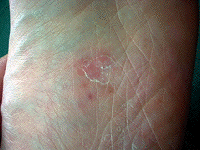

実験前の足の写真。

中央部分の赤い斑点が水虫です。 |